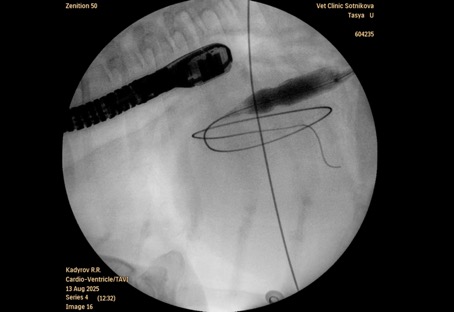

Баллон раздувался до рабочего давления (8–10 атм) в течение 10–15 сек. для создания постоянного сообщения между предсердиями. В ряде случаев требовалась повторная инсуффляция для достижения адекватного диаметра дефекта. В ходе процедуры осуществлялся интраоперационный контроль положения проводника и баллона с использованием эхокардиографического контроля и С-дуги (рис. 3).